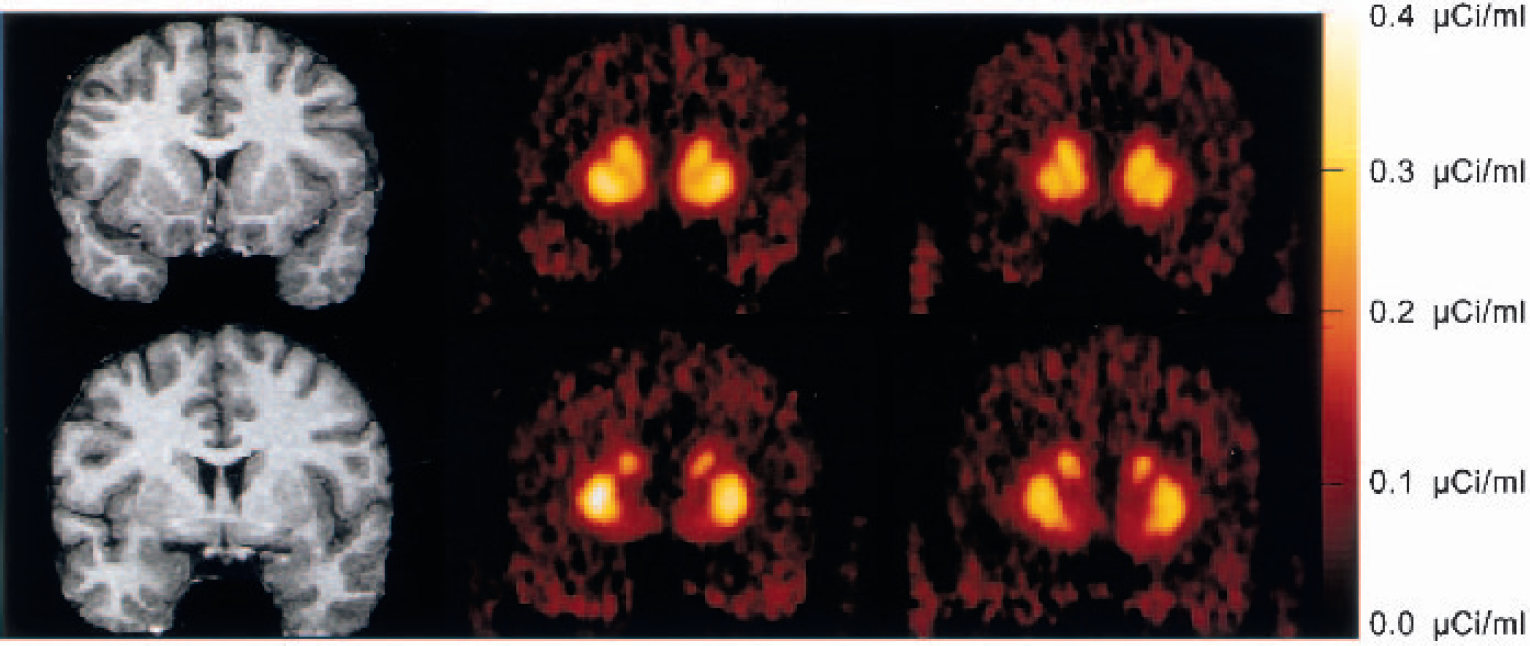

Figure 2 illustrates the time–activity curves of [11C]raclopride during the bolus–plus–constant-infusion experiments obtained under control conditions and after injection of amphetamine in the same subject. Figure 3 shows the PET images of [11C]raclopride distribution at baseline and after amphetamine in the same subject.

Activity in the striatum (triangles) and cerebellum (circles) during bolus plus constant infusion of [11C]raclopride at baseline (closed symbols) and after administration of amphetamine (0.3 mg/kg, open symbols). Amphetamine administration induced significant decrease in striatal activity but no change in cerebellum activity. Equilibrium measurements were obtained during the 40- to 90-minute interval.

Coregistered magnetic resonance imaging scans and positron emission tomography (PET) [11C]raclopride coronal images (